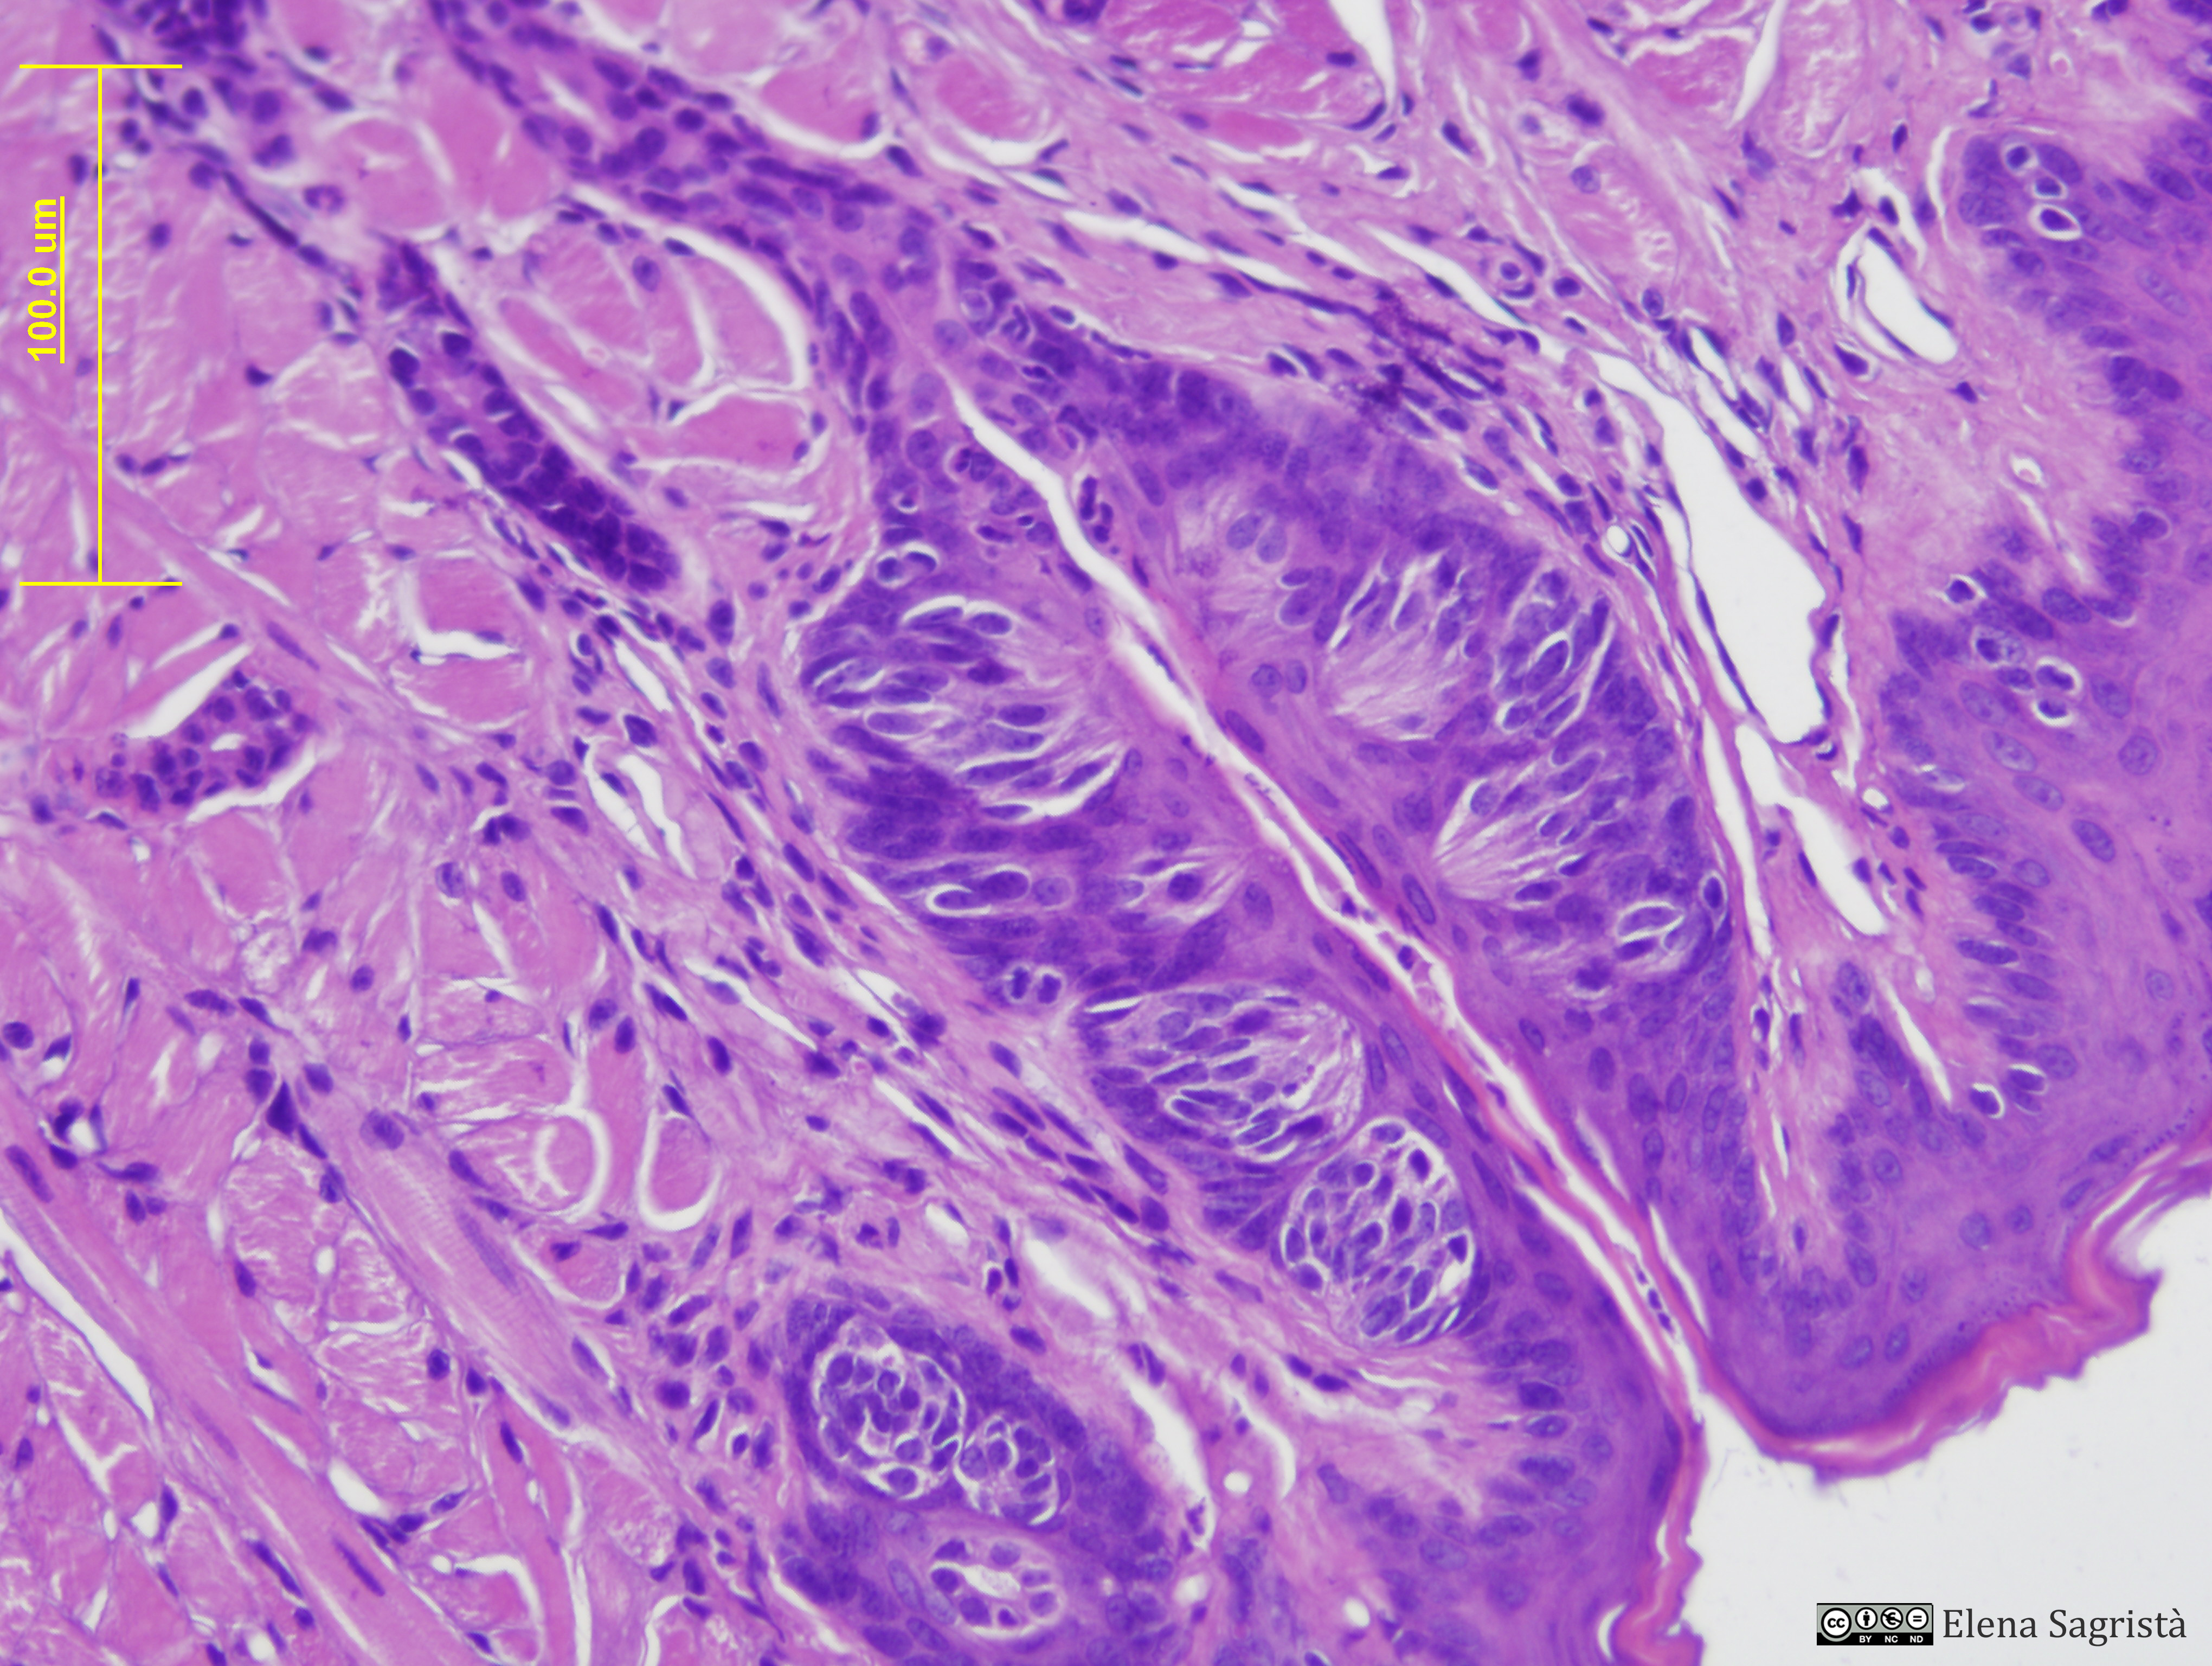

Histologia imatges: 14 Llengua

Imatges de preparacions histològiques de Llengua. Microscopia òptica.